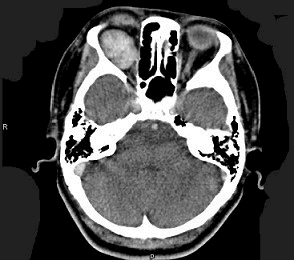

患者,女性70岁,因双眼视力骤降半天就诊。检查:右眼视力0.02,左眼0.03,结膜无充血,角膜透明,角膜后沉着物阴性,瞳孔对光反射对称、迟钝,晶状体轻度混浊,玻璃体无混浊;视乳头充血水肿。(如图)请问首选需行哪种检查()

-

患者,女性70岁,因双眼视力骤降半天就诊。检查:右眼视力0.02,左眼0.03,结膜无充血,角膜透明,角膜后沉着物阴性,瞳孔对光反射对称、迟钝,晶状体轻度混浊,玻璃体无混浊;视乳头充血水肿。

如VEP为各波潜伏期延长、波幅下降;眼底荧光造影为视盘高荧光;视野为巨大中心暗点;CT无异常;视力下降经验光试镜无法矫正。则诊断为()

- 患者,女性70岁,因双眼视力骤降半天就诊。检查:右眼视力0.02,左眼0.03,结膜无充血,角膜透明,角膜后沉着物阴性,瞳孔对光反射对称、迟钝,晶状体轻度混浊,玻璃体无混浊;视乳头充血水肿。下列有关本病的治疗原则中错误的为()